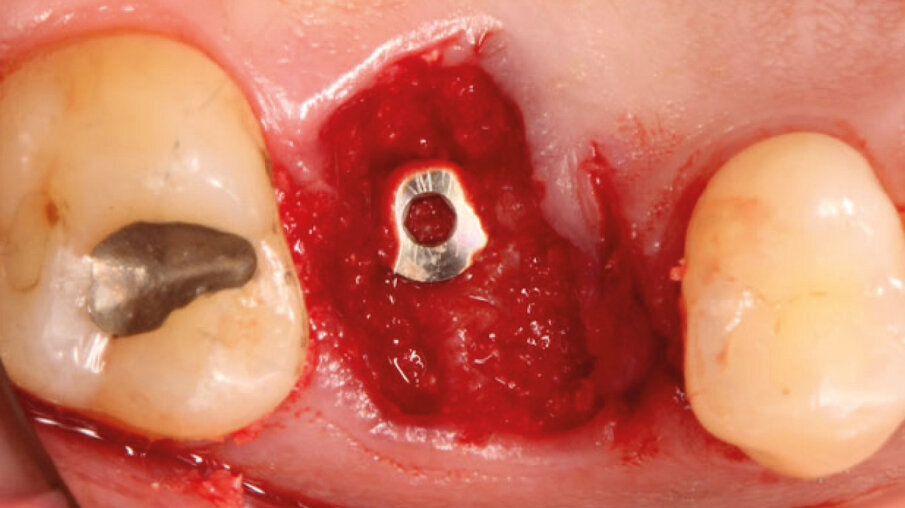

Dopo l’esecuzione dell’anestesia locale, il dente è stato rimosso e l’alveolo pulito dai residui del legamento parodontale. È stato inserito l’impianto (Zimmer TSV, Zimmer, Parsippany) 4.1 x 11,5 TSVM posizionato seguendo il protocollo consigliato dal produttore (Fig. 3). L’impianto è stato inserito a livello della cresta alveolare. È stato avvitato lo scan-abutment (Zfx Intrascan Matchholder, Zfx,). È stata rilevata un’impronta ottica intra-operatoria dell’emiarcata in cui è stato posizionato l’impianto con lo scan abutment (Fig. 3). Il gap tra l’osso vestibolare e l’impianto è stato riempito con Bio-Oss (Geistlich Pharma) (Fig. 4). Al termine della chirurgia è stato progettato e fresato il provvisorio, che è stato applicato appena pronto, dopo aver inserito la matrice in collagene volumetricamente stabile Fibro-Gide (Geistlich Pharma) precedentemente imbibita con il gel a base di polinucleotidi e acido ialuronico Regenfast (Officine Bio-Farmaceutiche Mastelli), al di sotto della vite stessa (Figg. 5, 6). Data l’accuratezza della vite non sono state necessarie suture. Al termine della procedura è stata eseguita una radiografia di controllo (Fig. 7).

Fig. 4_Inserimento implantare con zappatura del gap con Bio-Oss.